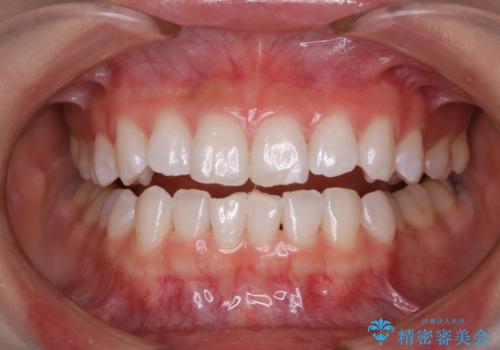

- オフィスホワイトニング希望で1日で白くしたいとのことでした。

オフィスホワイトニングのエクセレントコース(¥29700)を行いました。